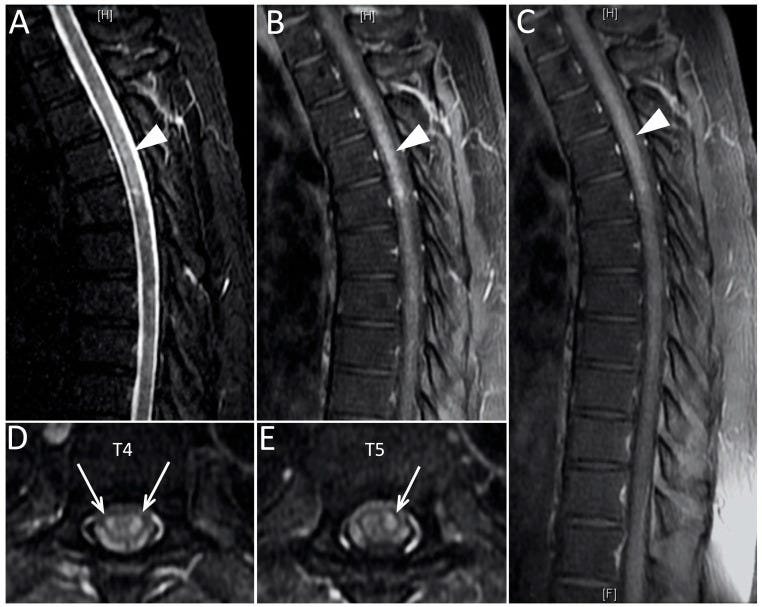

Results: All patients had typical features of ATM with acute onset of paralysis, sensory level and sphincter deficits due to spinal cord lesions demonstrated by imaging. There were 23 males (53%) and 20 females (47%) ranging from ages 21- to 73- years-old (mean age, 49 years), with two peaks at 29 and 58 years, excluding 3 pediatric cases. The main clinical manifestations were quadriplegia (58%) and paraplegia (42%). MRI reports were available in 40 patients; localized ATM lesions affected ≤3 cord segments (12 cases, 30%) at cervical (5 cases) and thoracic cord levels (7 cases); 28 cases (70%) had longitudinally-extensive ATM (LEATM) involving ≥4 spinal cord segments (cervicothoracic in 18 cases and thoracolumbar-sacral in 10 patients). Acute disseminated encephalomyelitis (ADEM) occurred in 8 patients, mainly women (67%) ranging from 27- to 64-years-old. Three ATM patients also had blindness from myeloneuritis optica (MNO) and two more also had acute motor axonal neuropathy (AMAN).